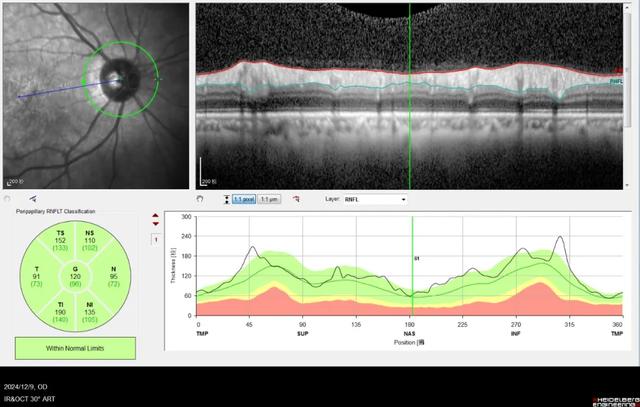

RNFL右眼

RNFL左眼

难道是球后视神经炎?但对于球后视神经炎而言,患者年龄偏大,视力及视野损伤也远较球后视神经炎来的轻,所以我认为不是。视网膜电图(ERG)也证实了我的想法,P50及N95波峰并未明显下降,提示整体视网膜及视神经功能还是可以的。mf-ERG提示双眼黄斑中央振幅明显下降,所以还是黄斑问题导致的视力下降。

既然锁定调查方向在黄斑,那接下来最应该做的就是黄斑OCT检查。在经过半个小时左右的散瞳后,OCT结果提示,双眼黄斑中心凹视网膜外层结构明显受损,椭圆体带不连续,色素上皮不规则隆起。